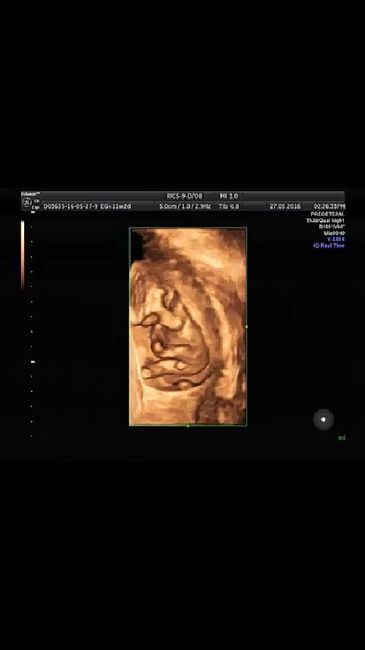

Cómo saber si ya es hora de tener hijos

Les comparto este articulo por que a mi la verdad me pone a pensar mucho dar este paso de ser padres ya que es una responsabilidad muy grande, y la verdad no me siento...